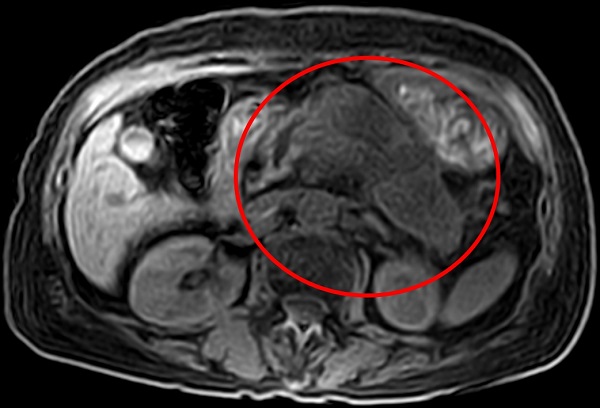

▲ 胰臟癌症狀為胃悶、食慾不振,常與消化系統毛病混淆,造成延誤就醫。(圖/北投健康管理醫院提供)

沈彥君表示,想要知道胰臟是否健康,必須仰賴磁振造影、電腦斷層,前者無放射線,較為安全,胰臟癌早篩率可達9成;至於超音波檢查,常會被胃腸的空氣擋住視野,成為致命的疏漏。